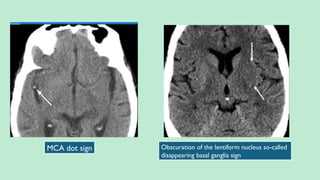

1. DenseVessel Sign:

a. Hyperdense MCA Sign (M1) – Earliest of all (in about 30%). Most specific but

least sensitive. MCA Dot Sign – MCA in the Sylvian Fissure (M2/M3).

Obscuration of the lentiform nucleus so-called

disappearing basal ganglia sign

MCA dot sign

Insular ribbon sign: Hypodensity

and swelling of the insular cortex